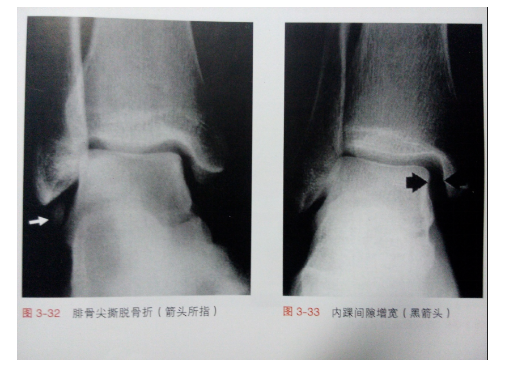

定义:胫骨远端前方或距骨颈异常增生的骨赘突入胫距关节内,在踝关节背屈时产生撞击,造成活动受限和疼痛。多见于运动员及舞蹈演员,侧位X线片是这类损伤最为常用的影像学检查方法。

分级

根据X线片对前方踝关节撞击症进行分级

Ⅰ级:胫骨远端前方出现骨赘(≤3mm)

Ⅱ级:胫骨远端前方出现骨赘(≥ 3mm)

Ⅲ级:胫骨远端前方骨赘合并距骨颈部骨赘

Ⅳ级:胫骨远端前方骨赘与距骨颈部骨赘互相接触

病因:后外侧结节(三角骨突)损伤